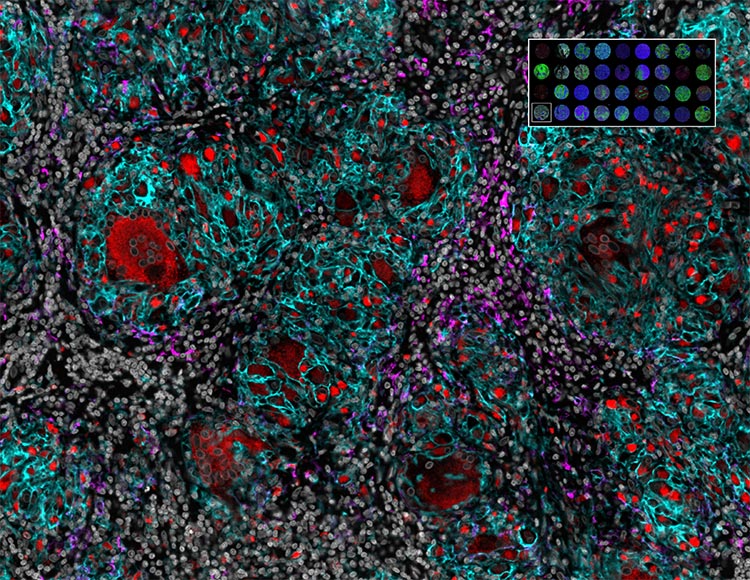

Orion 14 plex imaging of patient-derived pancreatic ductal adenocarcinoma organoids. Image courtesy of Yana Zavros, University of Georgia School of Medicine.